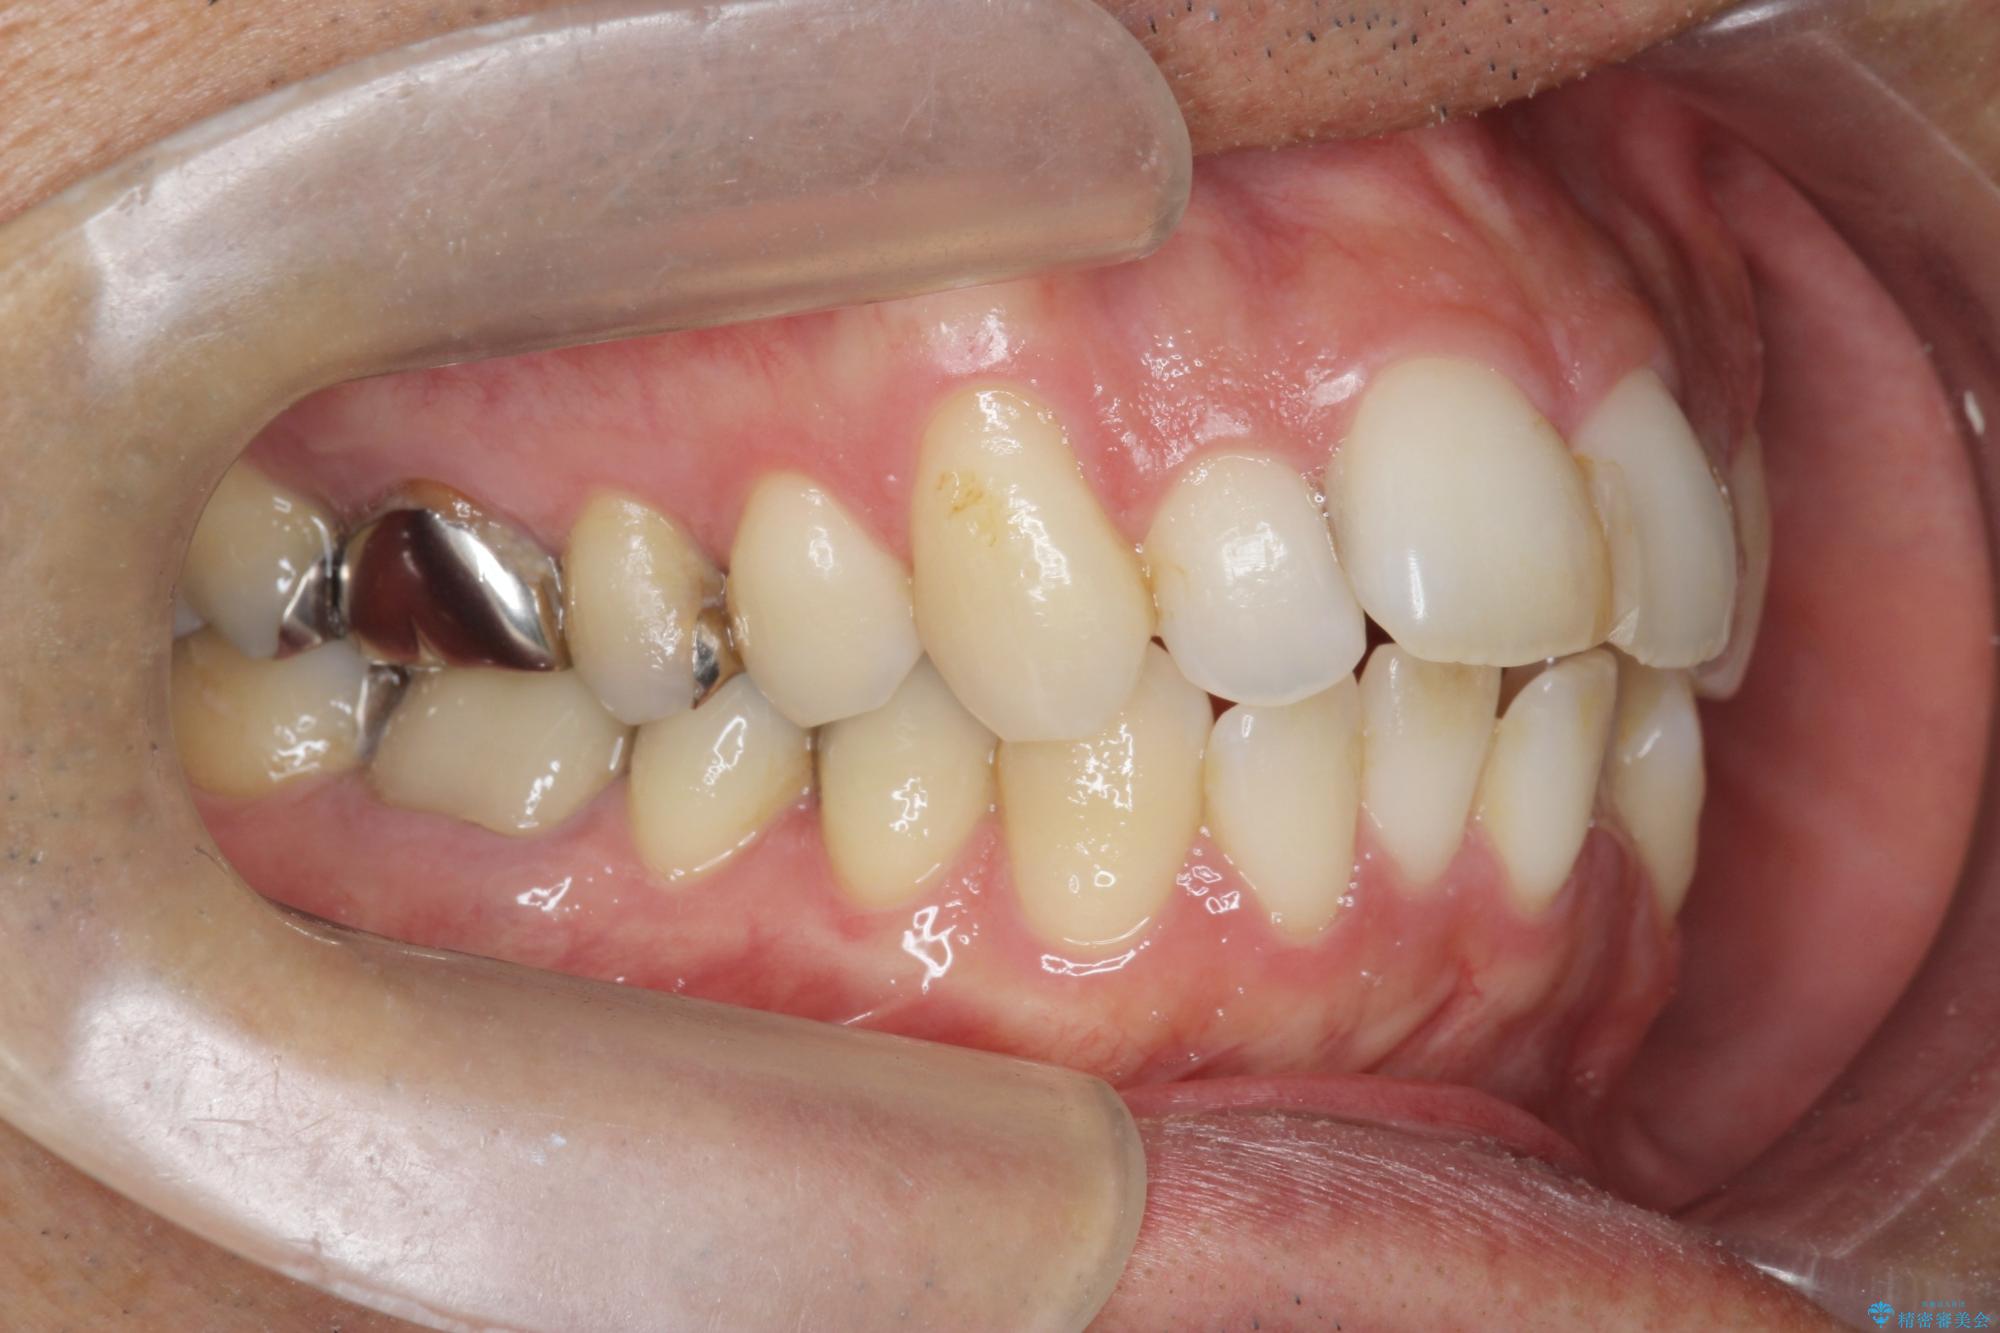

- 突き出た前歯の角度の改善と虫歯治療の改善を求めて来院されました。

虫歯を除去したのち、マウスピース矯正治療を行い、歯並びやがたつきを改善したのち、セラミックに置き換えることで審美性の向上を計画します。